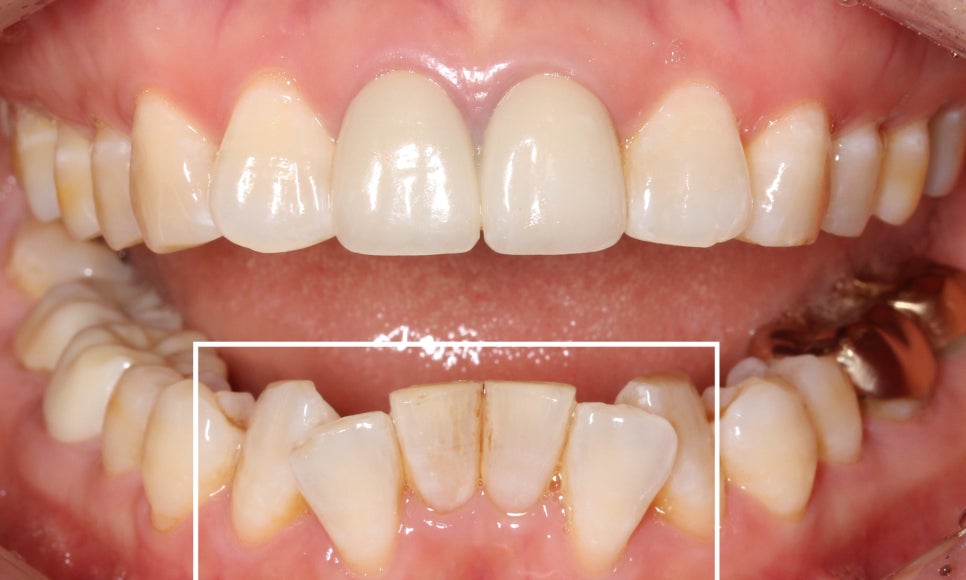

약 9개월의 아랫니 부분교정이 끝난 뒤

치아의 모습입니다~

삐뚤거리던 아랫니가 많이 정리된 모습이죠?

들쭉날쭉하던 아랫니의 전치부도

아랫니 부분교정(2D교정)으로

고르게 맞춰진 모습입니다!

윗니에 가려져서 거의 보이지 않았던

아랫니도 아랫니 부분교정(2D교정)을 통해

정상적인 교합상태로 바뀐 모습입니다~

반대쪽 모습도 과하게 물리는 모습 없이

깔끔하게 교정되었어요 : )